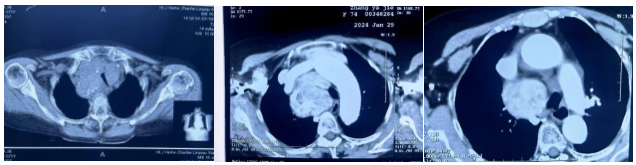

患者由于肿瘤长期压迫心包和肺动、静脉,已经出现心包积液,并伴有严重的房颤、三尖瓣重度反流、肺炎。哈医大肿瘤医院头颈外科鼻咽喉口腔二病房项丞教授经过专业判断,发现肿瘤的来源是甲状腺,虽然颈部的包块并不明显,但肿瘤向下生长,从颈部一直长到胸部,成为了“压在心里的大石头”。

由于患者病情复杂,项丞教授团队组织哈医大肿瘤医院介入科、影像中心、心内科、胸外科、麻醉科、呼吸内科、腔镜室等多学科联合会诊,为张大娘制定了颈部切口游离颈部肿瘤,并利用腔镜辅助分离胸部、上纵膈、心包上肿瘤的治疗方案。